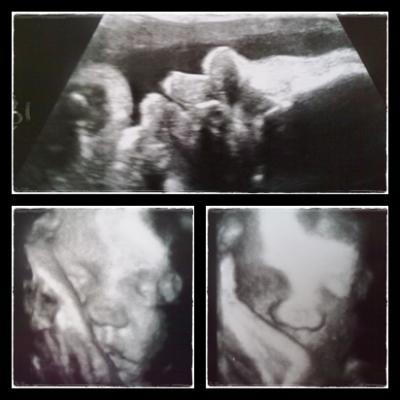

Hallo Mädls! Ich hatte heute wieder FA-Termin und meinem kleinen Cian geht es prächtig! Hier ein paar Daten (bin heute 35+0): Größe: 42cm Gewicht: 2191g Kopfumfang: 31,2cm Bauchumfang: 29,83cm Lage: II.Schädellage Zervixlänge: 27mm Mein Kleiner ist wirklich ein kleines, zierliches Kerlchen!!! Aber laut FA alles Bestens!!! Glg, Claudia mit BabyCian an Bord

Bild zu Mein kleiner BauchWicht - Forum für August - Mamis